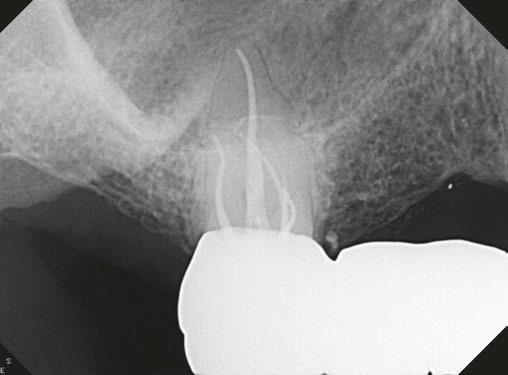

The Cone Beam Computed Tomography (CBCT) by J. Morita is now an indispensable tool, utilized for every case. It provides invaluable 3D anatomical insights that were previously unattainable, allowing us to:

• Accurately diagnose complex anomalies and pathology

• Thoroughly evaluate tooth restorability before treatment initiation.

• Reduce retreatment rates by mapping canal anatomy and identifying all present canals.

• Facilitate truly minimally invasive “ninja” access by enabling precise, image-guided entry.

Dr. Neil Singh reviewing CBCT images

The human body and teeth involved are complex, as are the root canal systems, and prior to the imaging techniques available today, everything was based in two dimensions. By implementing a protocol of 3-D analysis, we have opened research and file systems/obturation techniques to improve in areas they may not have had foresight to change.

A minimalist approach often translates to maximal initial investment in technology and diagnostics. This isn’t driven by financial gain but by an unwavering commitment to superior patient care, both in treatment and, critically, in accurate diagnosis. We frequently encounter cases where unnecessary root canal procedures could have been avoided entirely if a CBCT scan been utilized from the get-go.

Also, minimalism in practice means more in cost, so we’re doing it for patient care in treatment and in diagnosis. I can’t tell you how many patients didn’t need a root canal but got one; had someone just done a CBCT, the whole thing could’ve been avoided.